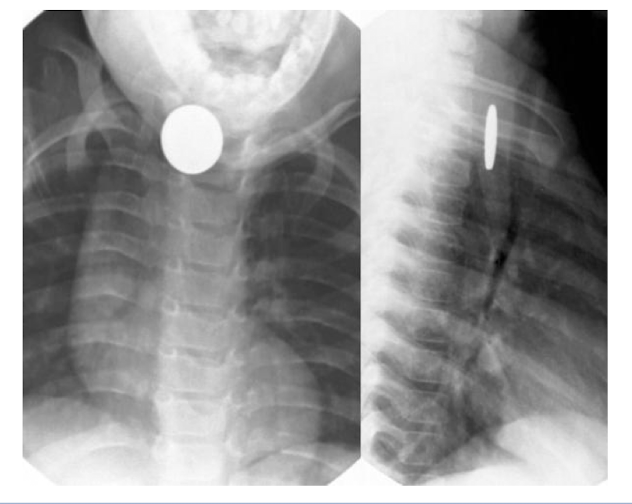

What are the more common GI tract abnormalities of the pediatric population?

Foreign body

What is shown on the pediatric imaging?

Esophageal Foregin body